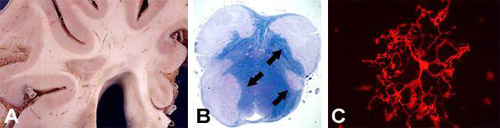

Oligodendrocytes in health and disease

The Kuhlmann lab studies the molecular mechanisms of myelination and remyelination. The myelinating cells of the central nervous system (CNS) are oligodendrocytes. In many CNS diseases (e.g. multiple sclerosis (MS)) oligodendrocytes are destroyed resulting in demyelination and impaired neuronal function. Our research focuses on mechanisms regulating oligodendroglial cell death and remyelination, a repair process in the CNS. The aim of our research is to contribute to the development of new treatment strategies for demyelinating diseases.

In current projects we analyze molecular mechanisms regulating oligodendroglial migration as well as the functional role of selected signalling cascades on oligodendroglial differentiation and remyelination. To address our research questions we use a wide range of experimental techniques and approaches. We study human tissue sections, primary rodent cell cultures, organotypic cerebellar slices and different demyelinating animal models.